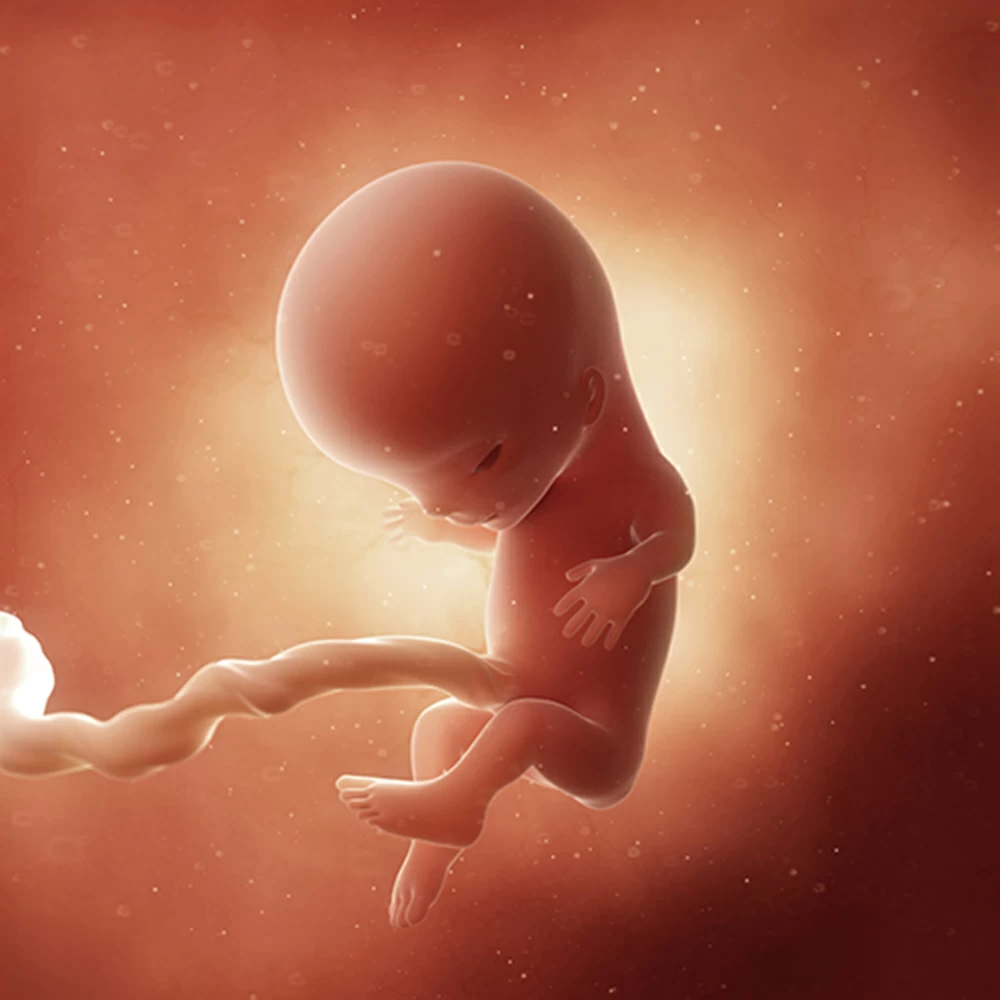

Неделя № 11

К концу этой недели копчиково-теменной размер плода увеличивается до 4-5 см.

Тело плода остается непропорциональным: мелкое туловище, большие размеры головы, длинные руки и короткие ноги, согнутые во всех суставах и прижатые к животу.